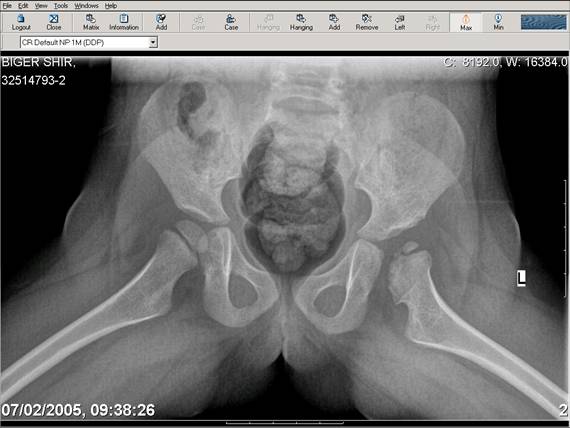

Здравствуйте, уважаемые коллеги.Обратилась девочка 6-ти лет из жалобами на боль в левом т/б суставе,хромоту Из анамнеза : ребенок лечился с рождения по поводу врожденного вывиха бедер. В возрасте 3- х лет в одной из клиник была выполнена остеотомия таза по Пембертону и варизирующая остеотомия бедра слева, справа - остеотомия таза по Солтеру и остеотомия бедра. Посоветуйте тактику лечения. С уважением Ihor

Smotritsya parshivo konechno(pseudoacetabulum,partial AVN), no v6 let ya by popytalsya ispravit chto moghno:shortening (ne boyatsya ubrat bolshoi fragment),derotation(30 gradusov ne bolshe)+pelvic osteotomy in true acetabuluam area.Obyazatelno takghe open reduction with wide capsular exposure.

Navernoe Dega

Chto by ne byt goloslovnym posilau vam svoi sluchai gde sdelal vse chto napisal vyshe

Уважаемой Ihor! Следует дообследовать ребенка, проведя РКТ или МРТ. Необходимо установить взаимоотношение головки бедренной кости и вертлужной впадины слева, оценить угол антеторсии и истинный ШДУ. Далее решать вопрос об оперативном лечении. Скорее всего показана деторсионно-варизирующая остеотомия в межвертельной области левого бедра и остеотомия таза типа Солтера (хотя ацетабулярный индекс великоват, т.е. более 30-35 градусов). Справа следует понаблюдать и периодически проводить курсы ФТО и ЛФК. Если Вы не имеете опыта реконструктивной хирургии ТБС у детей, то лучше отправить пациента к детским ортопедам. АИФ